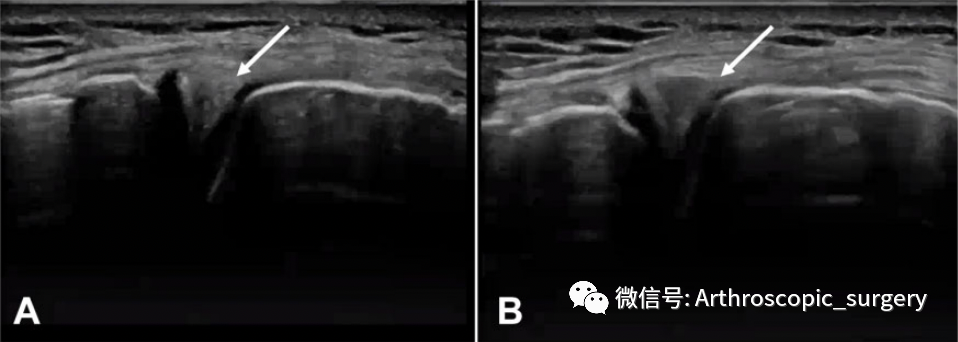

半月板作为一个动态的结构,有学者提出在B超下动态观察半月板体部的外凸情况,但是这一诊断由于主观偏差性较大,暂时没有得到大家的普遍认可,但是其提出动态观察在很大程度上更加符合半月板的功能。

动态超声检查。(A)休息时,半月板不存在外凸的现象(箭头);(B)内翻时,内侧半月板被挤压出来(箭头)。